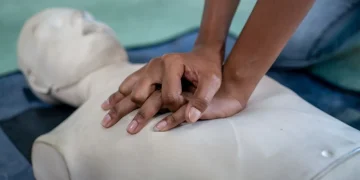

Read moreÇfarë duhet të bëni nëse dikush po pëson një atak kardiak

Nëse dyshoni se dikush ka kaluar në arrest kardiak, ka disa hapa të thjeshtë që mund të ndërmerrni menjëherë që mund të nënkuptojnë ndryshimin midis jetës dhe vdekjes. Rreth 70%...